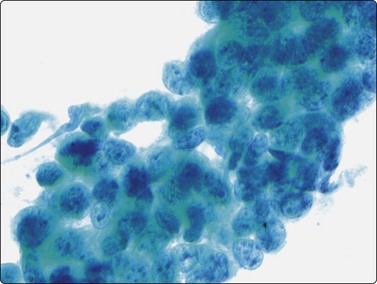

Malignant lymphoma

Over 90% of non-Hodgkin lymphomas in children are high-grade lymphomas.14 The most common types are T and B lymphoblastic, Burkitt and anaplastic large cell lymphoma while diffuse large B-cell lymphoma is less common.20 Lymphoblastic, Burkitt and diffuse large cell lymphomas in children can be mistaken for any other SRCTs on the basis of morphology alone. Within the paediatric population, each of these lymphomas has distinct clinical features which are important to recognize.71 Lymphoblastic lymphoma typically affects young teenage boys, and is a common cause of a mediastinal mass as well as peripheral, usually supradiaphragmatic, lymphadenopathy. Most of these are T-cell immunophenotype and positive for terminal deoxynucleotidyl transferase (TdT). Aspiration smears are highly cellular with a singly dispersed monotonous population of lymphoblasts with no evidence of true intercellular cohesiveness. The cells are twice the size of normal lymphocytes. Nuclei demonstrate finely granular chromatin with inconspicuous nucleoli, and only a thin rim of delicate cytoplasm (Fig. 17.12). Abundant lymphoglandular bodies are present in the background and serve as an important diagnostic clue of the lymphoid lesion. Neuroblastoma enters into the differential diagnosis as it can present as a primary mediastinal lesion. However, intercellular cohesion, nuclear molding, typical Homer-Wright rosettes and absence of lymphoglandular bodies favor the diagnosis of neuroblastoma.

image

Fig. 17.12 Lymphoblastic lymphoma

Highly cellular smears contain a monomorphic population of lymphoblasts with no true intracellular cohesiveness. The cells demonstrate uniform round nuclei with finely dispersed chromatin, inconspicuous nucleoli, and a thin rim of cytoplasm. Numerous lymphoglandular bodies are readily identifiable in the background.